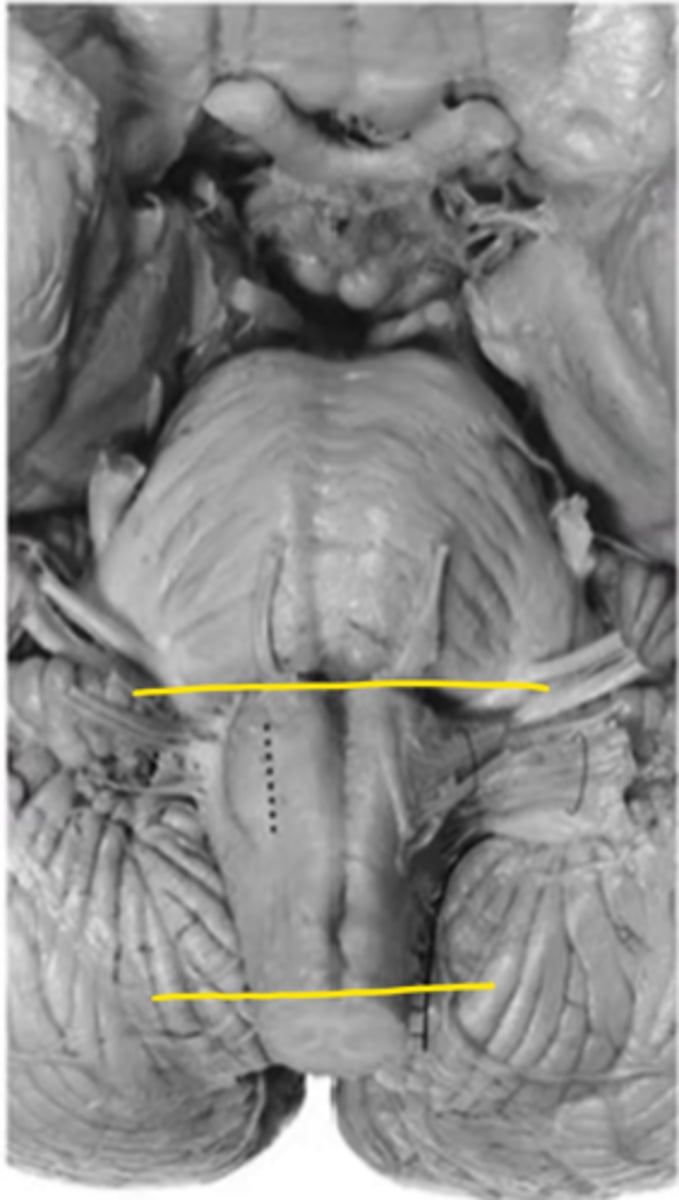

medulla

ID the area

open medulla

closed medulla

ID the brainstem level